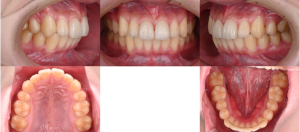

※初診時口腔内写真(全体)

初診時の状態では、上下のいちばん奥の歯がまだ生えそろっていない段階でした。

また、上の前歯が前方に出ている噛み合わせの傾向が見られました。

※初診時口腔内写真正面

青色の矢印で示している部分を見ると、歯と歯の間にすき間がある状態であることがわかります。

白い線で上の前歯の形をなぞってみると、歯の大きさや形のバランスに乱れがあることが確認できます。

また、黄色い丸で囲んだ部分には、**上唇の内側と歯ぐきをつなぐヒダ(上唇小帯)**が見られます。このヒダが発達している場合、上の前歯の間にすき間ができやすくなることがあります。

※前歯の噛み合わせ

下の前歯が、上の前歯の歯ぐきに触れそうになるほど深い噛み合わせであることが確認されました。このような噛み合わせは、下あごがやや小さい場合に見られることがあります。